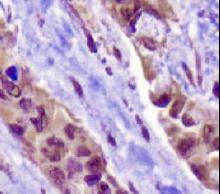

TP53

IHC of paraffin-embedded Carcinoma of Human lung tissue using anti-TP53 mouse monoclonal antibody.